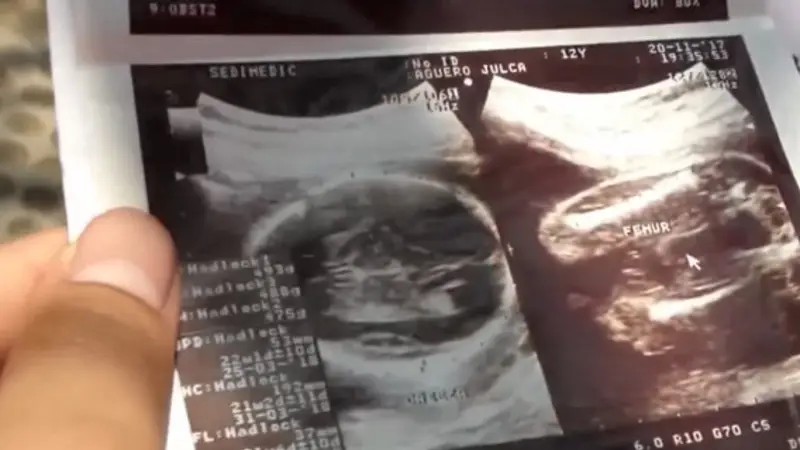

En la gestión 2024 en el país se han registrado más de 20 mil embarazos en niñas y adolescentes entre 10 y 19 años de edad.

En la gestión 2024 en el país se han registrado más de 20 mil embarazos en niñas y adolescentes entre 10 y 19 años de edad. Este tipo de casos es una situación difícil de sobrellevar para muchas familias; en este sentido, la experta psicóloga Valentina Richter da una serie de pautas orientadas a la prevención.

Un dato alarmante sobre los embarazos en adolescentes es que el 23 % se da por violencia sexual sobre las menores de edad.